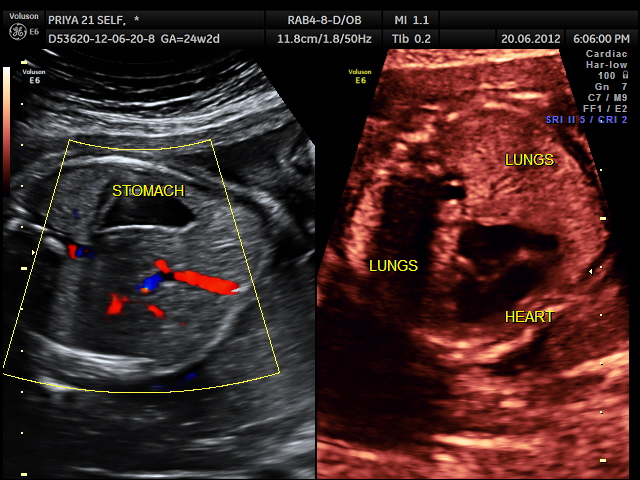

This was a 24 year old primi with history of consanguinity sent for evaluation of probable dextrocardia.

The following images were seen .

the following video shows right atrium and rt ventricle to be grossly dilated and the left atrium and left ventricle to be very small and hypoplastic.